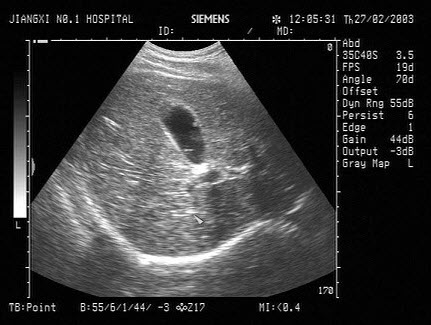

10、单项选择题

女,40岁,有时右上腹隐痛2年余。结合超声声像图,最可能的诊断为()

A.肝血管瘤

B.肝脓肿

C.小肝癌

D.转移性肝癌

E.肝囊肿